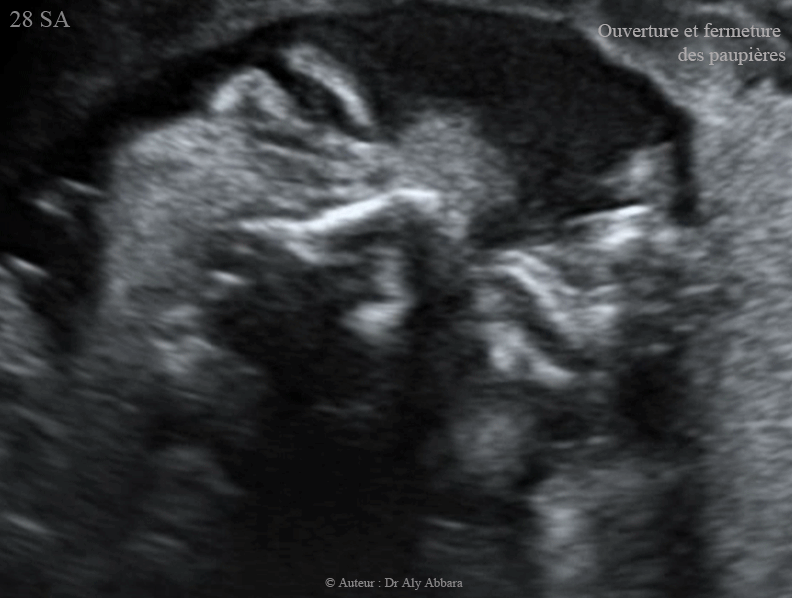

Mouvements d'ouverture - fermeture des paupières - foetus de 28 SA - حركات فتح وإغلاق الأجفان عند الجنين بعمر 28 أسبوع

Images échographiques animées montrant des mouvements d'ouverture - fermeture des paupières chez un foetus âgé de 28 SA.